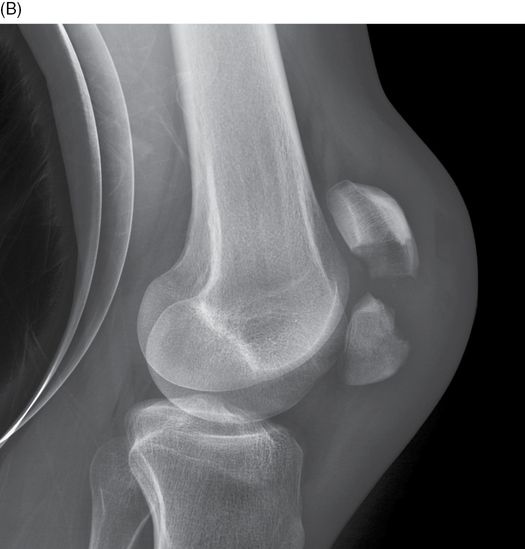

Avulsion Fractures of the Knee Imaging Findings and Clinical What Is A Buckle Fracture Of The Knee They're incomplete fractures — the bone is not broken all the way. Buckle fractures are a type of bone injury that happen in children. Commonly seen in athletes, stress. A buckle fracture is an incomplete fracture where one side of the bone buckles or bends on itself; “a buckle fracture describes a condition where one side of a bone bends. What Is A Buckle Fracture Of The Knee.

Avulsion Fractures of the Knee Imaging Findings and Clinical What Is A Buckle Fracture Of The Knee Commonly seen in athletes, stress. A stress fracture is a minuscule crack in the bone that is caused by repetitive use or trauma. “a buckle fracture describes a condition where one side of a bone bends and buckles on itself even though the other side of the bone is not disrupted,” explains dr. A buckle fracture is an incomplete fracture. What Is A Buckle Fracture Of The Knee.

Avulsion Fractures of the Knee Imaging Findings and Clinical What Is A Buckle Fracture Of The Knee Commonly seen in athletes, stress. A knee fracture involves damage to the patella bone at the front of the knee. It does not affect the other side. A buckle fracture is sometimes referred to as an “incomplete fracture,” because the break is only on one side of the long bone of the arm or leg. Buckle fractures are a type. What Is A Buckle Fracture Of The Knee.